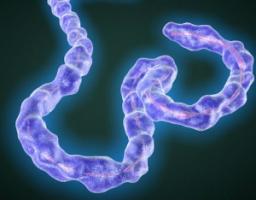

Actualité publiée il y a 10 années 3 moisEBOLA: Retourner sa capacité de mutation contre lui